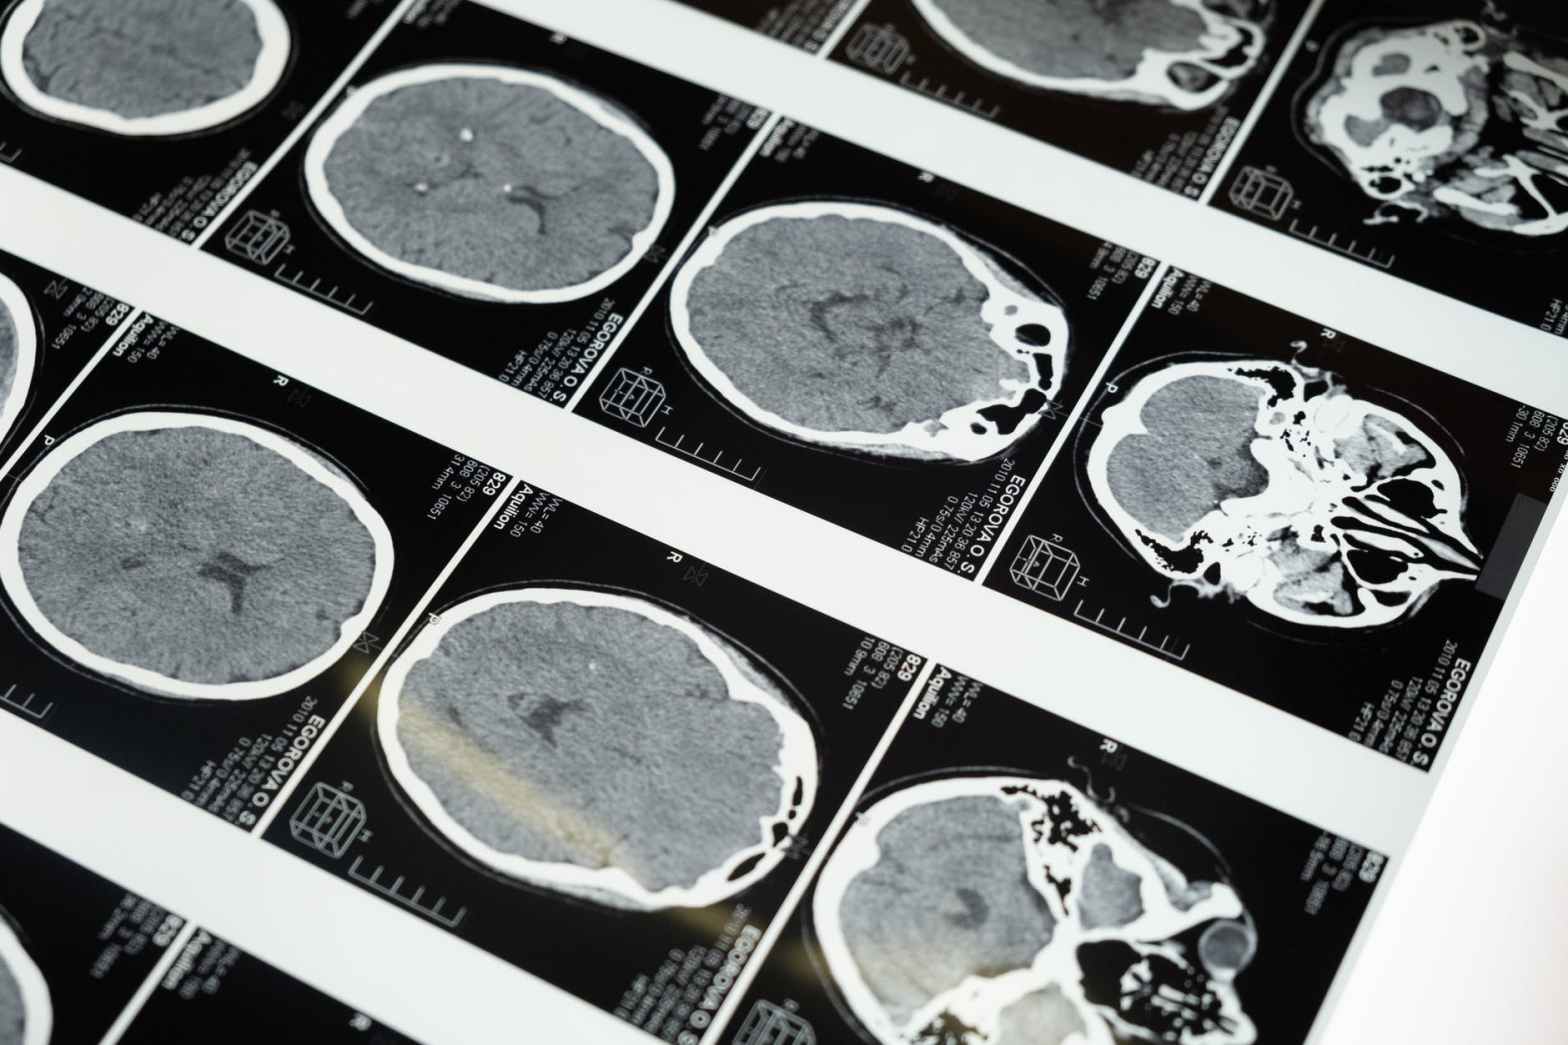

La tomografía es una técnica de diagnóstico por imágenes que utiliza rayos X para generar cortes transversales del cuerpo humano. Este estudio, conocido también como tomografía computarizada, ha revolucionado la medicina diagnóstica por su capacidad de proporcionar imágenes detalladas de órganos, tejidos y estructuras internas. Una de las inquietudes más comunes entre los pacientes esContinue reading “¿La tomografía emite radiación? ¿Es perjudicial?”

Los escaneos de tomografía computarizada (CT) son herramientas de diagnóstico increíblemente útiles que permiten a los médicos ver más de cerca lo que está sucediendo dentro del cuerpo. Se utilizan para examinar todo, desde huesos rotos y lesiones internas hasta tumores, y pueden ser una herramienta de diagnóstico vital en muchas situaciones. Sin embargo, comoContinue reading “Comprender la exposición a la radiación: ¿cuántas tomografías computarizadas son seguras para los humanos?”